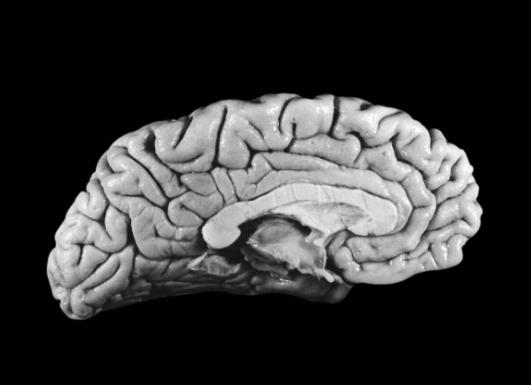

较早发表“轻脑”研究成果的是阿拉巴马大学的神经学教授保罗·安德森。经过10余年的研究他发现,爱因斯坦的大脑重量只有1230克(普通男子的大脑一般重1400克),因此他的大脑皮层比一般人薄。

安德森据此推测,爱因斯坦的大脑神经细胞密度比普通人高,使得传递信息的效率大大提高。安德森进而发现,爱因斯坦的右前额叶皮质(运动区)比对照组薄,可是皮质中的神经元数量与对照组无异。换言之,爱因斯坦的大脑皮质中,神经元密度较高。

这个“轻脑”发现有什么意义?安德森教授推论,一是人体的大脑神经元密度越高,则大脑记忆传导速度越快,对于逻辑思维能力的建立越有帮助;二是人体的大脑神经元分布网络越广,则大脑记忆存储量及大脑容积越大,而且人的综合记忆能力越强!也就是说,爱因斯坦的大脑皮质神经元有优异的传导效率与超卓的智慧天才。安德森教授也因这一发现获得了1998年诺贝尔医学奖的提名。